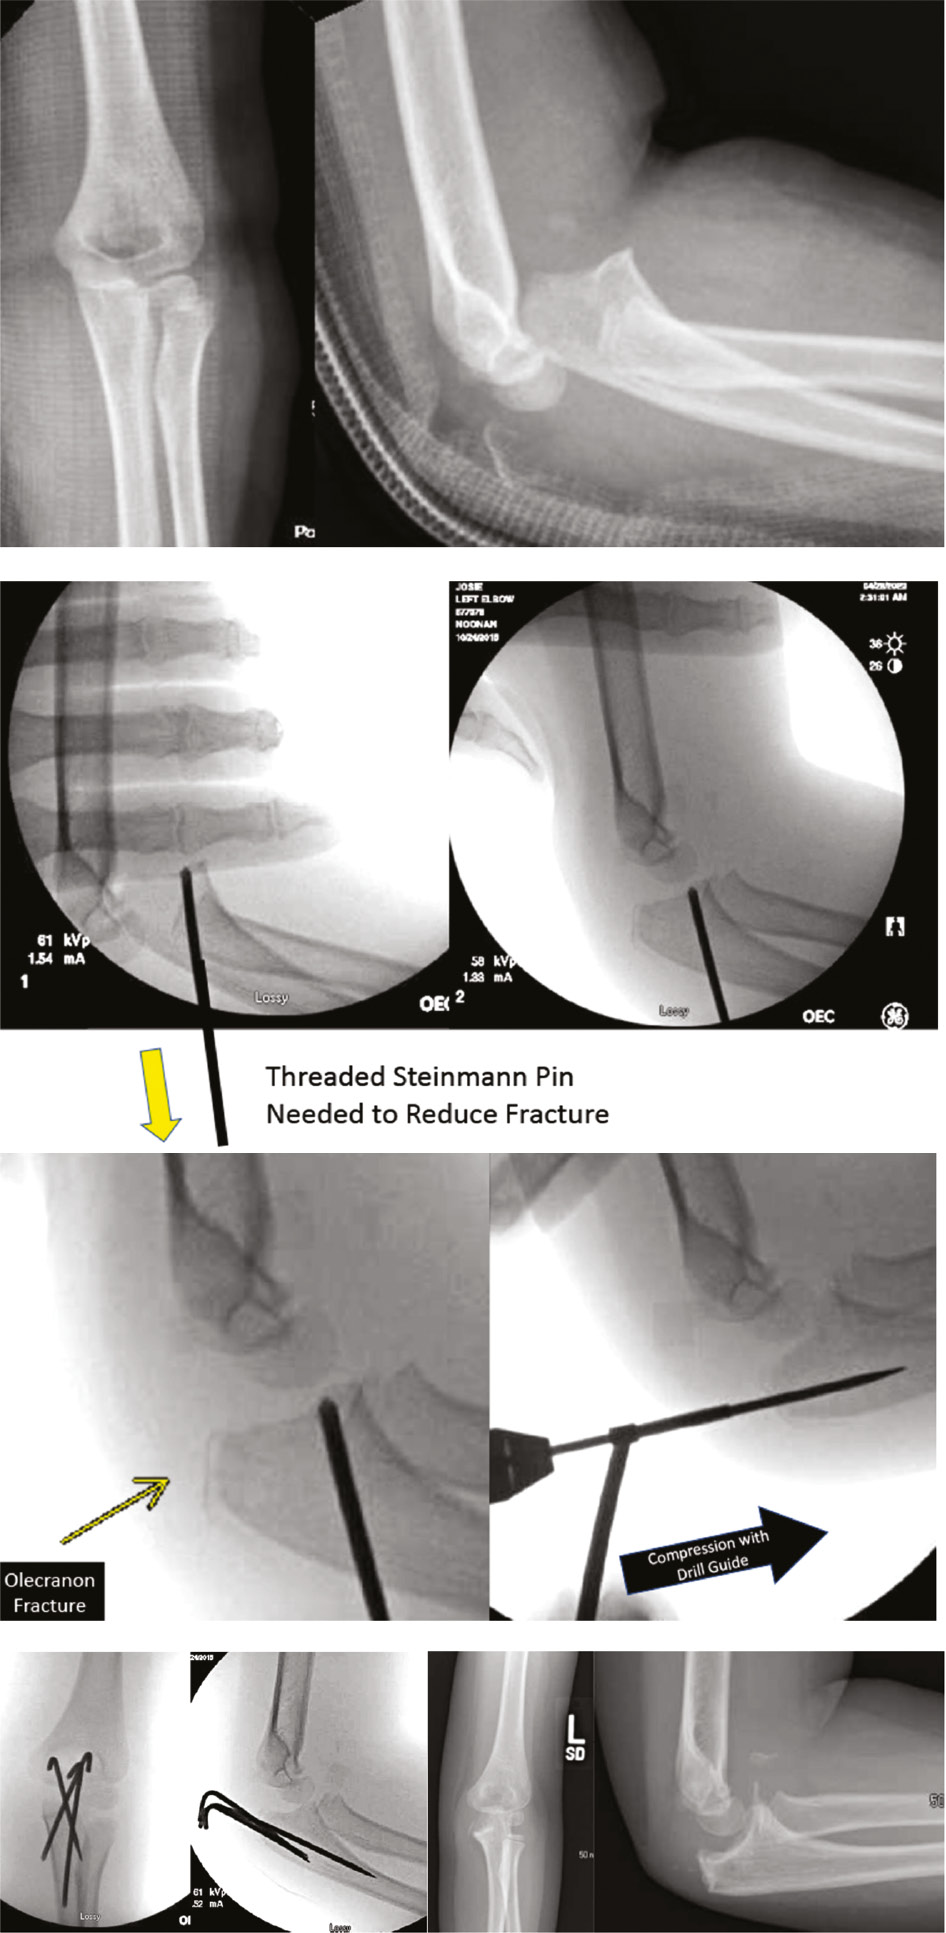

Olecranon

Olecranon fractures are uncommon in the pediatric population and can frequently be managed nonoperatively with good results.37 Generally, intraarticular fractures displaced greater than 2 mm are treated operatively, and options for operative management include tension band wiring or suturing, screw fixation, plate osteosynthesis, and percutaneous pinning.38 Tension band wiring is associated with high rates of symptomatic hardware, often necessitating reoperation for hardware removal.39,40 In pediatric patients younger than 10, tension band wiring is uncommon, and most surgeons use parallel partially threaded cannulated screws. Percutaneous pins are also an option.

With the patient in a supine position, the fracture is reduced either percutaneously or under direct visualization through a standard open approach. Two K-wires are passed percutaneously. The patient is then immobilized in a cast in 80 degrees of flexion.

Gortzak and coauthors proposed percutaneous pinning of olecranon fractures in conjunction with tension band suturing as a technique to address pediatric olecranon fractures while minimizing hardware complications. In this technique, an absorbable suture is tied in a figure-of-eight position, simulating tension band wiring.41 Percutaneous pins can also be used to treat the proximal ulna component of a Monteggia-type fracture (Figure 10).

Figure 10. This four-year-old presented with a fracture dislocation of her elbow which was irreducible in the OR. A threaded Steinmann pin in the olecranon facilitated reduction. The olecranon fracture was pinned percutaneously with a drill guide compressing cartilaginous apophysis. Follow-up x-rays showed an excellent result. Multiple K-wires were placed divergently to prevent displacement.